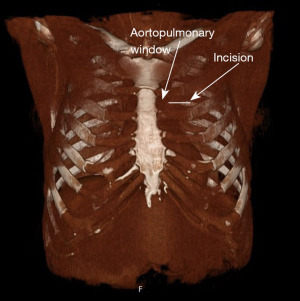

Anterior mediastinal masses can have a wide range of differential diagnosis. Surgical biopsies can be necessary to get sufficient material and an anterior mediastinotomy according to Chamberlain is a widely used option (1). This approach allows access to the anterior mediastinum avoiding a sternotomy. Figure 1 illustrates the modified Chamberlain mediastinotomy—i.e., without costotomy. This surgery is usually performed under general anesthesia and carries significant risks for the patients. The principal risks include compression of the superior vena cava leading to a cardiovascular collapse and complete airways obstruction by direct compression of the mass due to the relaxation needed for endotracheal intubation (2-4). We describe a case in which we proceeded to a surgical biopsy through an anterior mediastinotomy under hypnosis and local anesthesia. We present this case in accordance with the CARE reporting checklist (available at https://med.amegroups.com/article/view/10.21037/med-25-25/rc).

Surgeons proceeded with disinfection and draping once the patient was in state of well-being thanks to hypnosis. Local anesthesia was infiltrated through the cutaneous and subcutaneous planes and extended into the second intercostal space at the site of incision with 25 mL of lidocaïne 1% with adrenaline 1/200,000 was performed. Once the local anesthesia had taken effect, we made an incision of 5 cm at the level of the 2nd left intercostal space (Figure 4A, Video 1). This step was followed by dissection between the fibers of the pectoral muscle then by incision of the intercostal space. This allowed clear visualization of the waxy white tumor. We performed four cold blade biopsies in a square of 1 cm × 1 cm × 1 cm with a scalpel (Figure 4B). The biopsies were followed by careful hemostasis. During the procedure the pleural space was opened, and the resulting pneumothorax was evacuated only by aspiration before definitive skin closure (Figure 4C,4D). The surgery lasted 28 minutes.